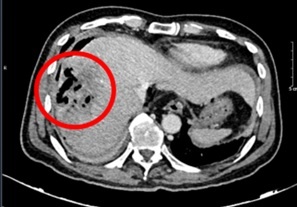

Hình ảnh chụp cắt lớp vi tính ổ bụng của bệnh nhân. Ảnh: BVCC.

Đáng chú ý, chỉ số AFP giảm mạnh theo thời gian, từ 648,1 ng/ml vào thời điểm bắt đầu điều trị xuống còn 9,2 ng/ml sau 20 chu kỳ, tiệm cận ngưỡng bình thường. Các kết quả chụp cắt lớp vi tính cũng ghi nhận khối u gan thu nhỏ rõ rệt, không còn tăng sinh mạch hay huyết khối. Kích thước u giảm từ 81 x 51 mm xuống còn khoảng 22 x 45 mm. Theo tiêu chuẩn RECIST 1.1, bệnh nhân đạt đáp ứng một phần.